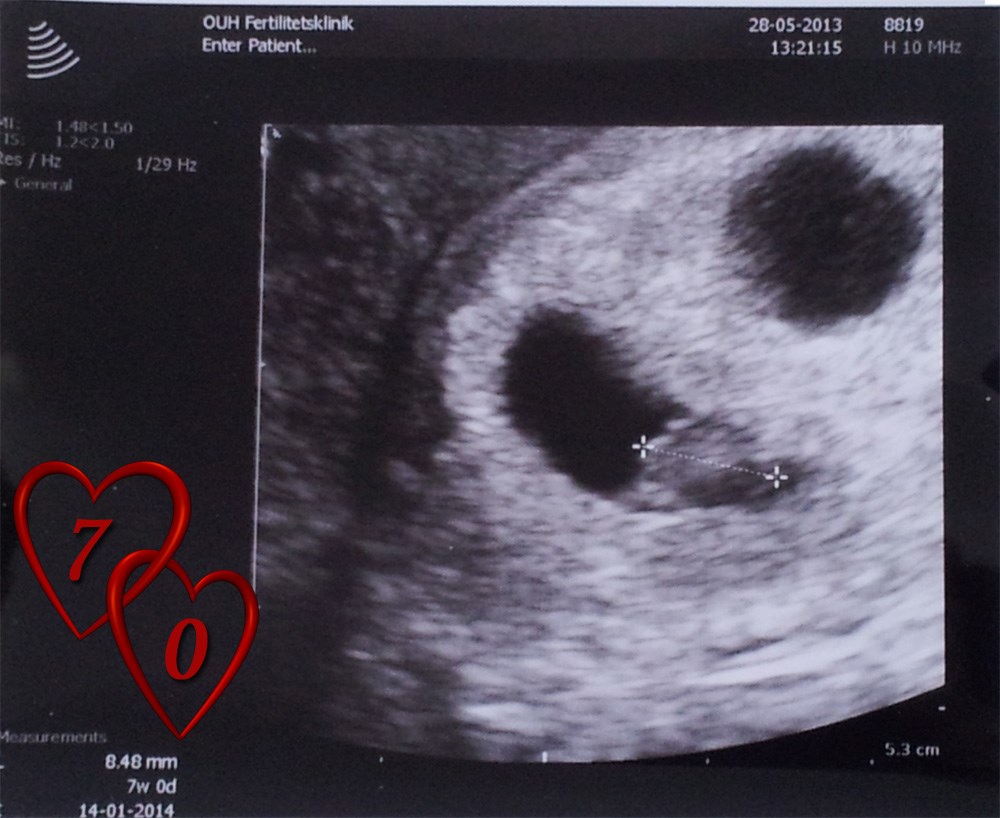

Men altså HCG gav os da et hint, da det var 659

Dog døde den ene i uge 9, så venter kun én lille bebs nu